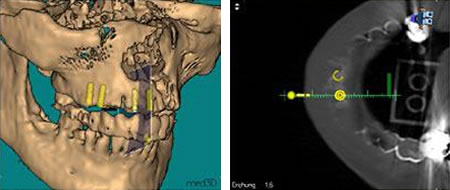

Im Vorfeld einer Implantation werden sehr genaue Informationen bezüglich des Knochenangebotes, der Knochenstruktur, der Wurzeln von Nachbarzähnen oder wichtiger anatomischer Strukturen wie Nerven oder die Kieferhöhlen benötigt. Die exakte Positionierung des Implantates unter Einbeziehung genannter Informationen ist für den Langzeiterfolg des Implantates entscheidend.

In schwierigeren Fällen, wenn zum Beispiel nur unzureichend Knochen vorhanden ist, die Lage der Nachbarzähne ungünstig erscheint oder evt. Nerven gefährdet sein könnten, werden im Vorfeld computertomographische Schichtröntgenaufnahmen benötigt. Während der Aufnahmen trägt der Patient bereits eine Schablone im Mund, welche die späteren "neuen Zähne" darstellt. Diese finden sich auf den Röntgenbildern wieder.

Die Röntgendaten werden in den Computer eingelesen. Es entsteht ein 3-dimensionales Abbild der Zahn-Kieferverhältnisse. Anhand dieses Bildes kann die exakte Position in Winkel und Tiefe der zu setzenden Implantate bestimmt werden. Die gewonnenen Positionierungsdaten können 1:1 auf die Schablone übertragen werden. In der Schablone werden entsprechend der Planung Bohrhülsen eingearbeitet, die eine genaue gewebeschonende Platzierung des Implantates, im richtigen Winkel und der richtigen Tiefe sicherstellen. Die Gefahr von Verletzungen der Nachbarzähne, Nerven oder sonstigen wichtigen anatomischen Strukturen, kann somit nahezu ausgeschlossen werden.